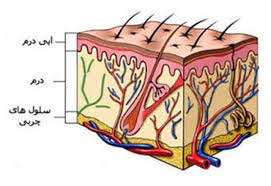

قیمت: 96٬000 تومان - دسته بندی فایل: پاورپوینتپاورپوینت آناتومی فیزیولوژی پوست و فرآیند التیام زخم (ppt) 141 اسلاید

فروش ویژه پاورپوینت حرفه ای آناتومی فیزیولوژی پوست و فرآیند التیام زخم / تعداد اسلاید: 141 اسلاید

قیمت: 96٬000 تومان - دسته بندی فایل: پاورپوینتپاورپوینت اصول گرفتن شرح حال و معاینه فیزیکی پوست (ppt) 140 اسلاید

فروش ویژه پاورپوینت حرفه ای اصول گرفتن شرح حال و معاینه فیزیکی پوست / تعداد اسلاید: 140 اسلاید